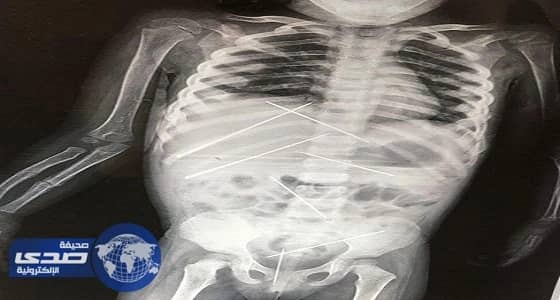

بالصور.. مسن هندي يغرس 7 إبر بجسد طفلة لمعالجتها من السحر الأسود